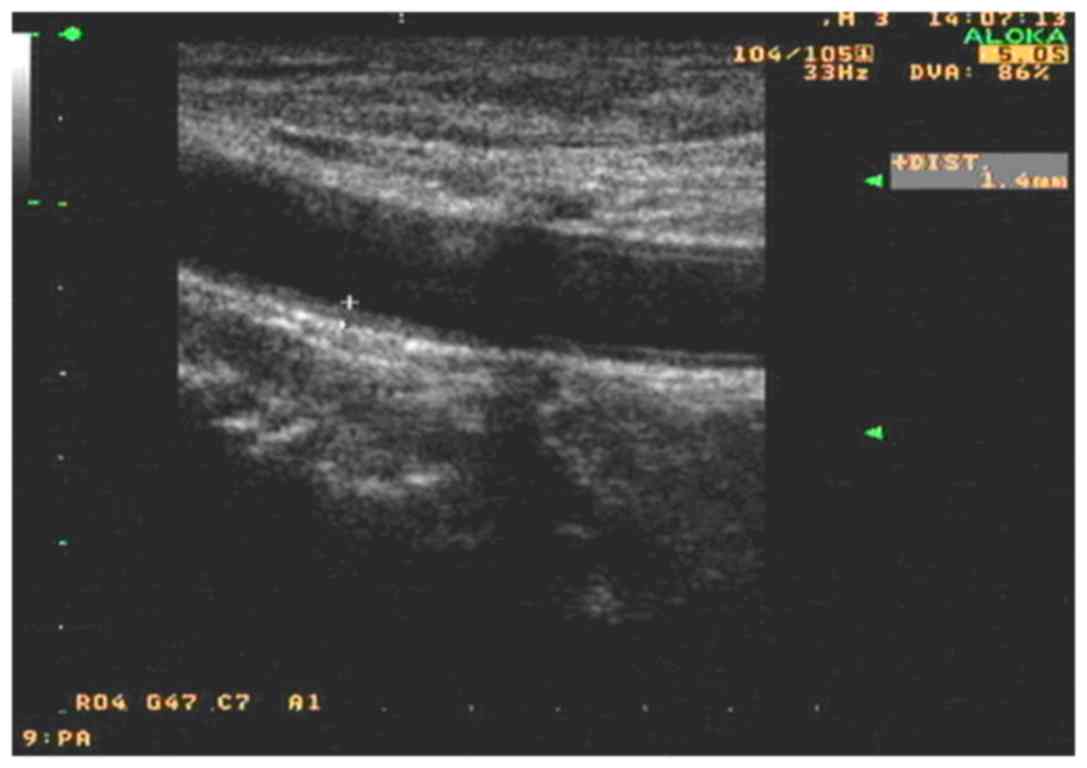

Carotid artery IMT

The IMTs are shown in Table II. After 12 weeks of allicin administration, the carotid artery IMT in the allicin group was significantly decreased compared with that in the control group (1.13±0.10 vs. 1.23±0.08 µmol/l; P<0.05). Compared with the baseline value, the IMT was significantly decreased after allicin treatment (P<0.01). The IMT was also significantly decreased in the control group (P<0.05), but that the decrease was greater in the allicin group (P<0.01). As shown in Figs. 1 and 2, after allicin treatment, the IMT was decreased from 1.4 to 1.0 mm.

Figure 2.

Carotid artery high resolution color Doppler ultrasonograph of a selected frame after allicin treatment of the same typical case as in Fig. 1.